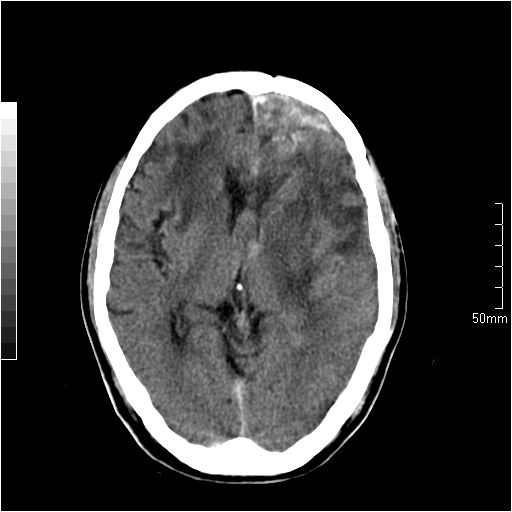

以下是引用天南地北在2007-6-25 12:39:00的发言:[br]有占位效应[br]支持术后复发

以下是引用zjzjr在2007-6-25 12:38:00的发言:[br]左侧复发,右侧转移。